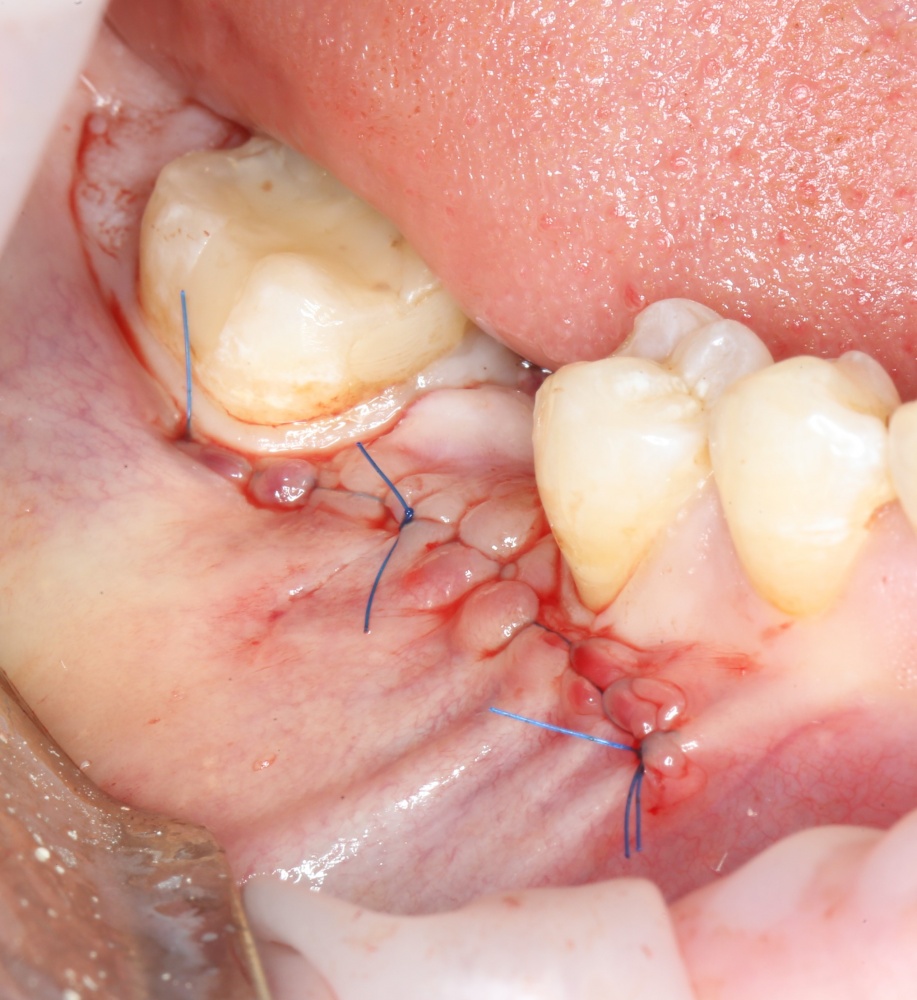

9. Наложение швов.

Я ни разу не испытывал каких-то проблем с ушиванием операционной раны. Как правило, её края сходятся достаточно легко без дополнительной периостотомии. Для наложения швов мы используем монофиламентные нерезорбируемые нити диаметром 5-0 (Resolone, Prolene, Полипропилен и др.).

Обычно, через день после операции рана выглядит вот таким образом:

Швы можно снять на 10-14 день.